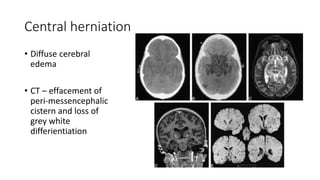

Central herniation

• Diffuse cerebral

edema

• CT – effacement of

peri-messencephalic

cistern and loss of

grey white

differientiation